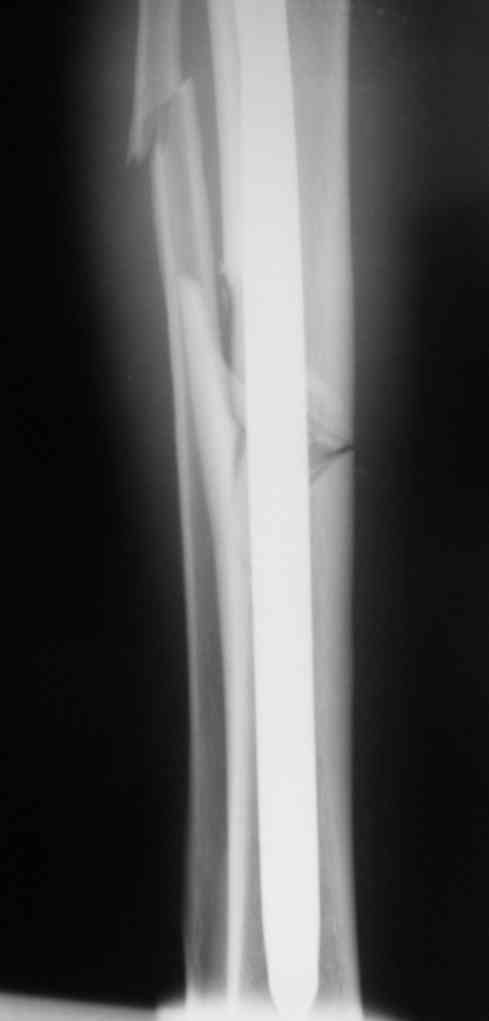

Дорогой Александр. Имею скромный опыт использования системы Fixion при переломах плеча, бедра и тибии. Всего 18 наблюдений с сентября 2006 г. Результаты отличные. Гвоздь индивидуален для каждого медуллярного канала. Легко имплантируется как в узкий, так и в деформированный канал. Это позволяет применять метод интрамедулярного остеосинтеза без ненужных потерь времени операции, флюороскопии и реально снижает крвопотерю и операционный риск. Удаление происходит без проблем. Особенно интересны больные с ипсилатеральными переломами бедра и голени.

В отношении ранней нагрузки при спиральных переломах лучше не торопиться. По данному случаю необходимо достигнуть исчезновения щели между штифтом и внутреним кортексом по Rg. А так картинка прекрасная - и длина сегмента и репозиция. Можно поздравить, коллега!